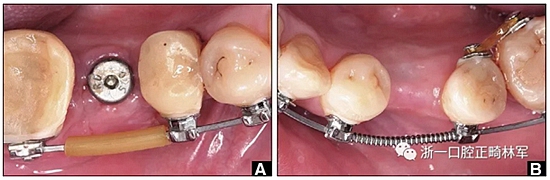

治療過程

圖14. A,用固定裝置右側(cè)保持下頜第一磨牙的間隙,并在弓絲上放置塑料護套以減少軟組織刺激; B,弓絲上的推簧維持通過正畸產(chǎn)生種植位置的間隙。